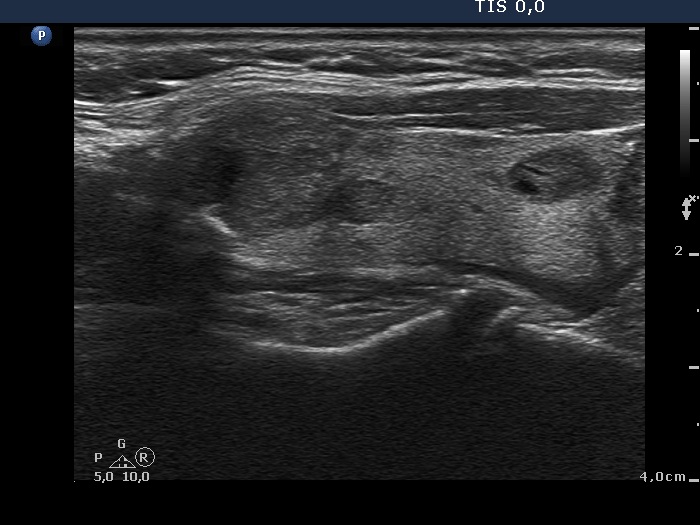

Ultrasonography. The thyroid was echonormal and contained numerous nodules with different echogenicities. A nodule in the upper pole of the right lobe and another one in the central part of the left lobe were relatively suspicious. The latter had irregular borders and presented perinodular blood flow and hyperechogenic granules.

The various nodules present lobulated and spiculated margins.